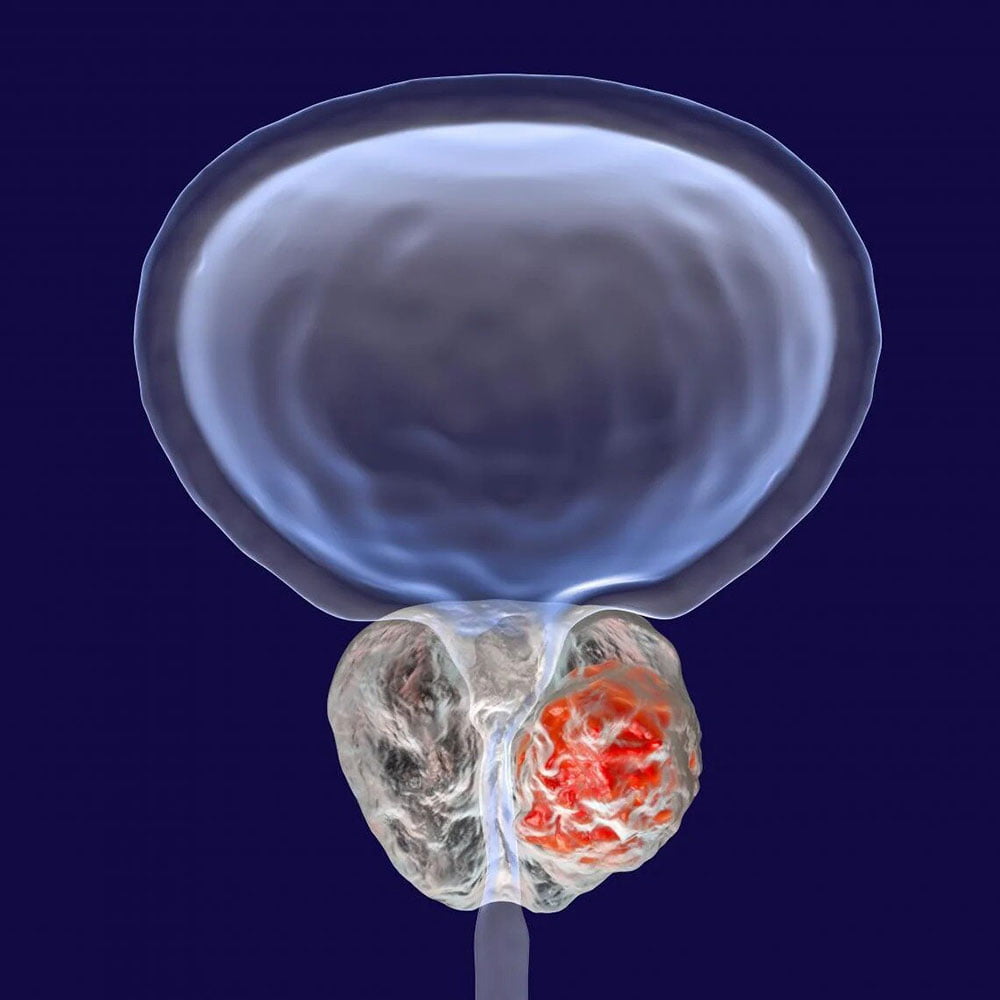

کلسیفیکاسیون پروستات چیست؟

«اختلال ناشی از رسوب عنصر کلسیم در غده پروستات (Prostate Gland) را کلسیفیکاسیون پروستات یا سنگ پروستات می گویند.»

سوال: پروستات چیست؟

پاسخ: پروستات غده ای کوچک با بافت عضلانی در دستگاه تناسلی مردان بوده که مجرای ادرار را احاطه می کند. بیشتر مایع منی در مردان در پروستات ساخته می شود.

کلسیفیه در پروستات چیست؟

کلسیفیه در پروستات به ته نشین شدن کلسیم در غده پروستات اشاره دارد که ناشی از رسوب این عنصر در غده پروستات است.